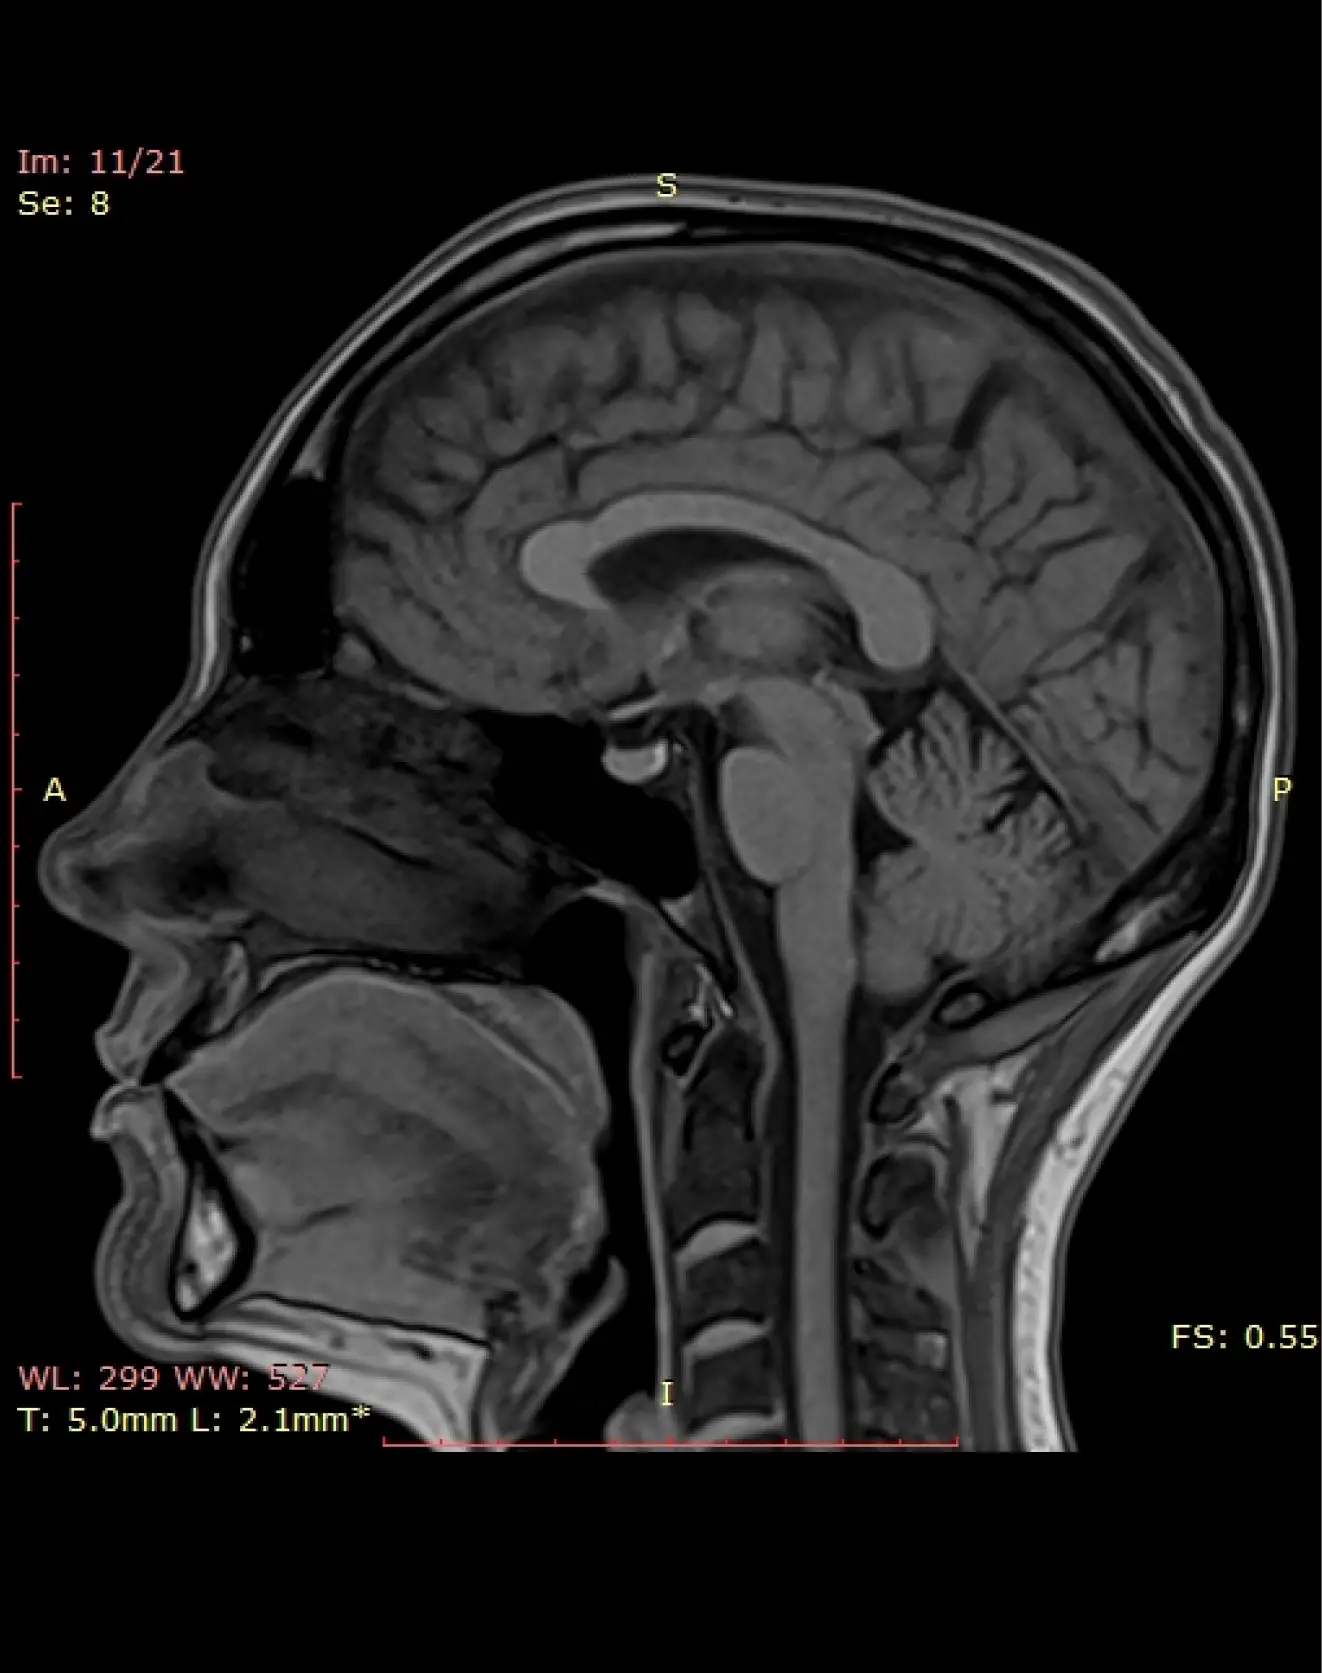

МРТ головного мозга (стандартное)

— Головные боли, головокружения, обмороки

— Нарушения чувствительности, судороги, ухудшение слуха или зрения

— Подозрение на инсульт, опухоль, воспаление, рассеянный склероз